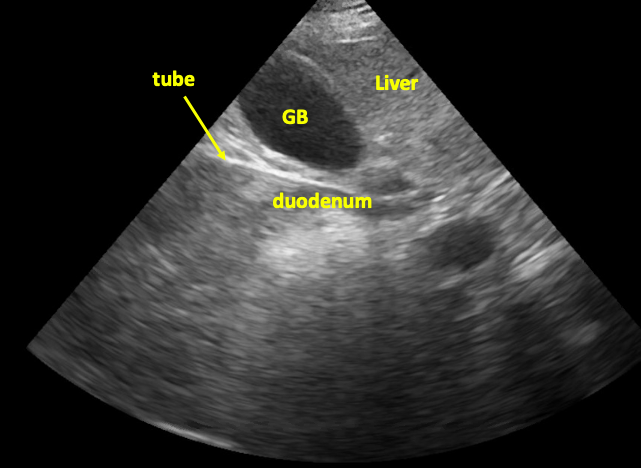

Tube in stomach/duodenum in short axis

The technique (continued)

If a separate NG is in place already, can suction out all air and fill with 60-180 cc fluid to optimize acoustic window.

In this image, tube in seen in duodenum in long axis.